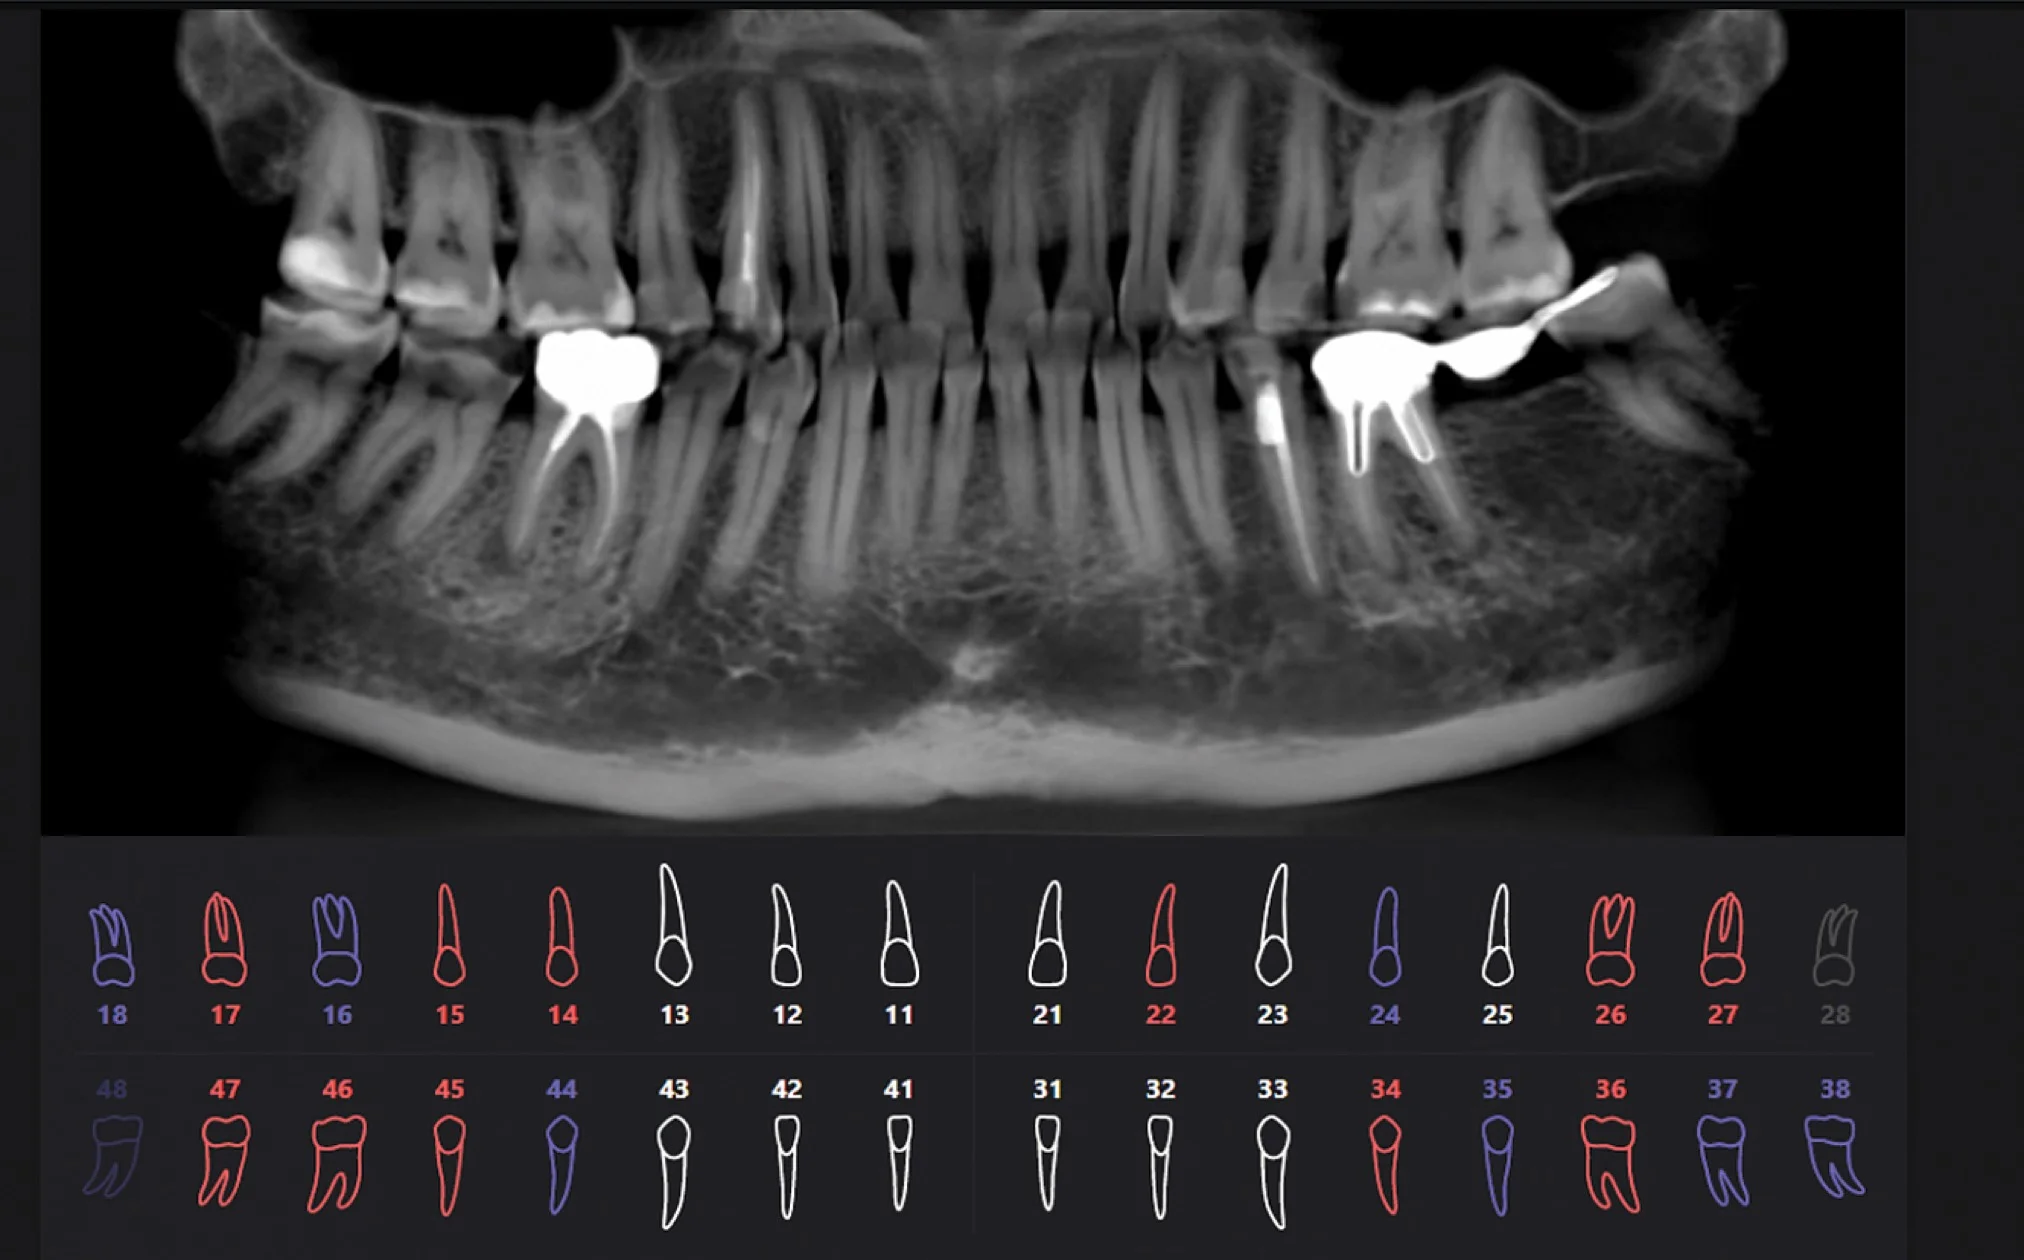

Результат работы искусственного интеллекта

Красным цветом показаны проблемные зубы, синим цветом — зубы с пломбами или ортопедическими конструкциями, белым цветом — здоровые зубы.

Сравнение подходов в изучении 3D снимков

Когда мнение врача и искусственного интеллекта отличается

Мнение врача и искусственного интеллекта иногда может отличаться, это сигнал для того, чтобы более глубокого изучить проблемную область, назначить ремтерапию, динамическое наблюдение.

Определяющее мнение всегда остается за врачом.